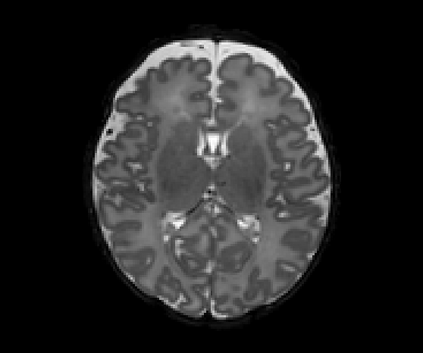

Real-world settings often do not allow acquisition of high-resolution volumetric images for accurate morphological assessment and diagnostic. In clinical practice it is frequently common to acquire only sparse data (e.g. individual slices) for initial diagnostic decision making. Thereby, physicians rely on their prior knowledge (or mental maps) of the human anatomy to extrapolate the underlying 3D information. Accurate mental maps require years of anatomy training, which in the first instance relies on normative learning, i.e. excluding pathology. In this paper, we leverage Bayesian Deep Learning and environment mapping to generate full volumetric anatomy representations from none to a small, sparse set of slices. We evaluate proof of concept implementations based on Generative Query Networks (GQN) and Conditional BRUNO using abdominal CT and brain MRI as well as in a clinical application involving sparse, motion-corrupted MR acquisition for fetal imaging. Our approach allows to reconstruct 3D volumes from 1 to 4 tomographic slices, with a SSIM of 0.7+ and cross-correlation of 0.8+ compared to the 3D ground truth.